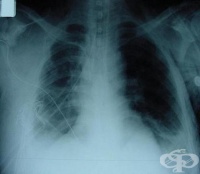

S27.4 Травма на бронхите

Заболявания

Увреждане на бронхите от механичен агент е травма на бронхите. Много често увреждането на бронхите с...

S27.7 Множествени травми на вътрегръдните органи

Проблемите на гръдния травматизъм са актуални, както от факта, че пострадалите са предимно млади хор...

S27.5 Травма на гръдната част на трахеята

Увреждане на трахеята при механична травма на гръдния кош е травма на гръдната част на трахеята. Пац...

S27.9 Травма на неуточнен орган в гръдната кухина

Гръдните травми заемат 36-46% от общия брой пострадали. Диагнозата травма на неуточнен орган в гръдн...